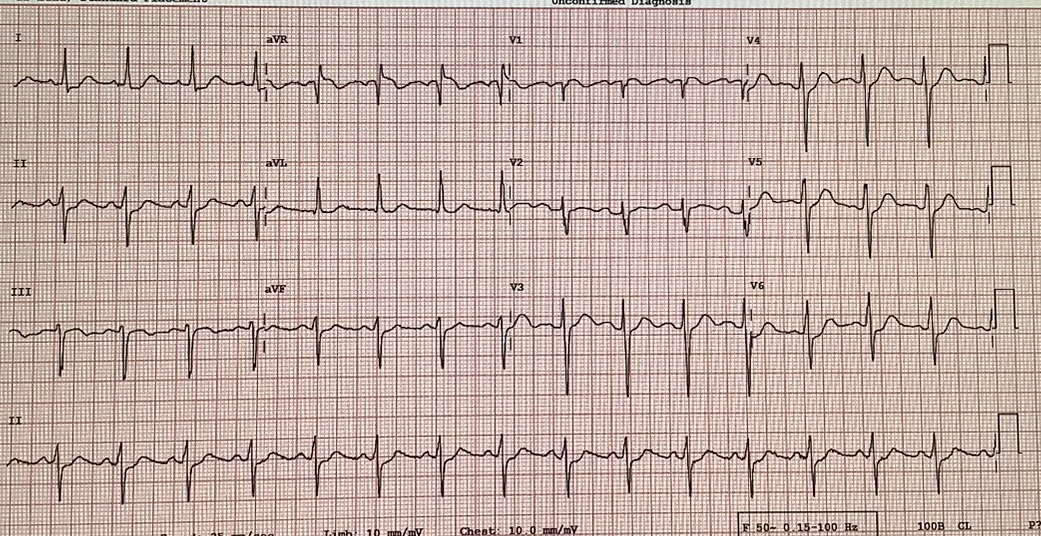

History Chief Complaint: 58 year old male presented with acute chest pain for 3 hours, radiating tothe left arm, associated with mild shortness of breath. No syncope orpalpitations.Past Medical History: Hypertension for 15 years, well-controlled withamlodipine and losartan.Dyslipidemia on rosuvastatin. Physical examination : no significant abnormal finding

Relevant Test Results Prior to Catheterization

Troponin T: 1.2 ng/mL (positive)

Relevant Catheterization Findings

Coronary Angiography: